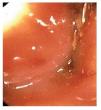

Paciente femenino de 46 años de edad, sin patológicos de importancia portadora de estreñimiento crónico de 26 años de evolución con autoprescripción. Inicia con dolor abdominal súbito de 2 días de evolución localizado en cuadrante inferior izquierdo, tipo cólico, sin náusea ni vómito, por lo que ingiere pancreatina con dimeticona sin mejoría, incrementando el dolor y agregándose náuseas, distensión abdominal e imposibilidad para canalizar gases, motivo por el cual acude a valoración. A su ingreso con vitales normales, con fascies de dolor, actitud forzada por dolor abdominal, mesomórfica. Mucosas parcialmente hidratadas, pálidas, cardiopulmonar sin alteraciones. Abdomen distendido, blando, doloroso a la palpación media y profunda de predominio en cuadrante inferior izquierdo, sin hiperestesia ni hiperbaralgesia. Rebote negativo. Peristalsis de lucha. Extremidades sin alteraciones. En radiografías simples de abdomen se observa distensión importante de colon proximal con nivel hidroaéreo en colon transverso y ausencia de gas en colon descendente y ámpula rectal (Imágenes 1 y 2). Se realiza colonoscopia con diagnóstico inicial de obstrucción colónica, introduciendo colonoscopio hasta una distancia de 120 cm, con lo que se llega a tercio distal de colon transverso impidiendo avanzar más el endoscopio por una zona de estenosis puntiforme, probablemente secundaria a torsión (Foto 1) intentando realizar detorsión sin éxito, por lo que es sometida a laparotomía exploradora encontrando torsión de colon transverso (Fotos 2 y 3) efectuando hemicolectomía derecha con transversectomía e ileosigmoideoanastomosis con engrapadoras, con una evolución favorable, siendo egresada al cuarto día por mejoría.

Foto 1. Zona de estenosis secundaria a volvulus.